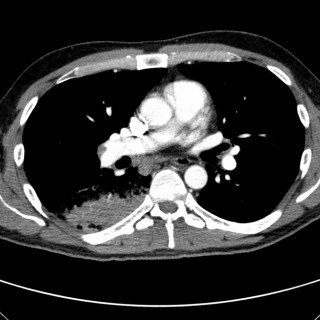

En kvinne fikk forverring av en hodepine som hadde debutert flere måneder i forveien. Hun utviklet deretter uvanlige kognitive symptomer og ble innlagt i sykehus. Pasienten, som var i 40-årene, hadde fra tidligere astma og var slankeoperert med gastrisk bypass. Det siste halvåret før innleggelsen hadde hun vært sykmeldt grunnet en oksipital, bilateral hodepine som oppsto under en arbeidskonflikt, men vedvarte trass i omplassering i ny stilling. Hodepinen hadde et fluktuerende forløp, med hodepinefrie dager. Den siste måneden var imidlertid hodepinen blitt konstant, og kvinnen hadde tatt...